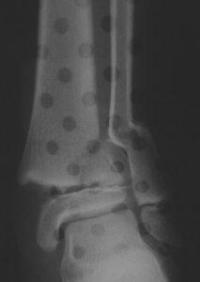

Exemples de décollements épiphysaires Salter 2